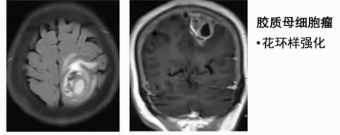

2) 胶质母细胞瘤:有明显占位效应,肿瘤内部多伴出血坏死和囊变,增强后呈花环样强化。